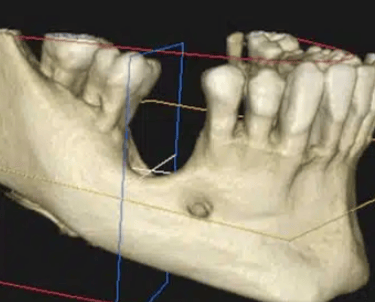

Atrofia ósea alveolar

La atrofia ósea alveolar es la pérdida de hueso en la mandíbula o el maxilar debido a la ausencia prolongada de dientes.

Los pacientes pueden notar que sus encías están hundidas y que las dentaduras no encajan bien.

El tratamiento puede incluir injertos óseos para preparar el sitio para la colocación de implantes.

Falta de hueso para implantes

La falta de hueso suficiente para la colocación de implantes puede ser una barrera para el tratamiento.

Los pacientes pueden ser informados de que no tienen suficiente hueso en la mandíbula o el maxilar para soportar un implante.

El tratamiento incluye técnicas de regeneración ósea, como injertos óseos, para aumentar el volumen óseo.